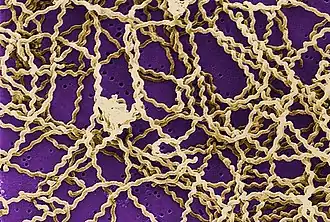

Leptospirosis is a zoonotic disease caused by bacteria of the genus Leptospira. Humans and dogs become infected through contact with water, food, or soil containing urine from infected animals. This may happen by swallowing contaminated food or water or through skin contact, especially with mucosal surfaces, such as the eyes or nose, or with broken skin. In dogs, transmission most commonly occurs by drinking puddle, pond, or ditch water contaminated by urine from infected wildlife such as squirrels or raccoons. The liver and kidney are most commonly damaged by leptospirosis. Vasculitis can occur, causing edema and potentially disseminated intravascular coagulation (DIC). Myocarditis, pericarditis, meningitis, and uveitis are also possible sequelae.[5]